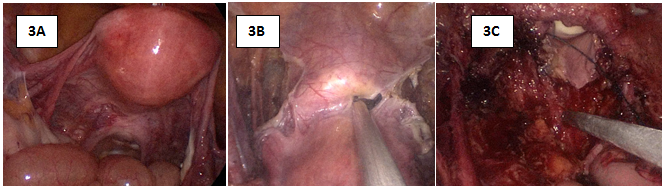

Figure 3 Intraoperative Images: 3A: there was no effusion and no adhesion in the pelvic cavity. Uterus and bilateral adnexa appeared normal.

Initially, the right-side infundibulopelvic ligament in high position was dissected (Figure 6). Next, the right-side anterior and posterior lobes of broad ligament were opened (Figure 7). After which the peritoneum incision was extended to in front of aorta abdominalis, exposing the right-side ureter. The lateral peritoneum was then cut to the bottom of right-hand round ligament of uterus (Figure 8). At this point the pelvic lymph node dissection was begun. The lymph nodes were dissected in the following order; common iliac artery nodes (Figure 9), external iliac nodes (Figure 10), inguinal nodes, obturator nest nodes (Figure 11), internal iliac nodes, and nodes of the main ligament of the uterus. After lymph node dissection the right uterine artery was ligated (Figure 12). The same process was repeated on the left side of the uterus. Peritoneal reflections of the uterus and rectum were separated, and the rectum was separated from the posterior wall and upper segment of vagina (Figure 13).

The vesicular peritoneum reflection was exposed; we then separated loose tissue between the bladder and the cervix to reach below the external cervical orifice. This exposed the interspace of the bladder and cervix. The gap of the para vagina was separated from both sides exposing the ligaments of the bladder and cervix; the intramural segment ureter was dissociated. (Figure 14) The bilateral rectal lateral fossa and pararectal pouch was opened to expose the bi-sacral uterine and the cardinal ligaments of the uterus. The bilateral sacrouterine ligament was removed 30mm from the cervix. The cardinal ligament was dissected, and the pelvic side wall, including the vagina cuff, was closed. Procedure time was four hours and thirty minutes, with an estimated blood loss of 50ml.